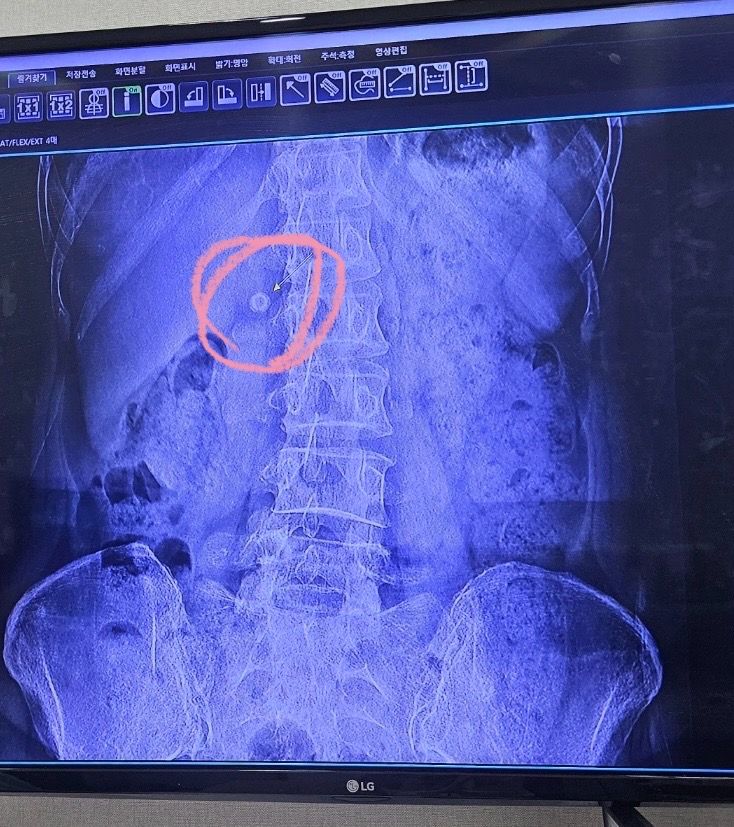

정형외과 엑스레이 사진찍었는데 흰색혹 같은거 혹시 뭔가요 ?

척추협착증이라 정형외과 엑스레이 찍었는데 흰색혹같은게 나와서 의사선생님이 내과가서 검사해보시는게 좋다해서 가봤어요!

내과외과 가봤는데 두분다 단추같은 물체가 찍힌것같다고 하시면서 별말 없으셨거든요 ..!

엑스레이 사진을 다시 찍어봤는데 똑같이 흰색 동그라미 물체가 보여서 의사선생님은 큰병원가서 검사해보시는걸 추천해드렸어요 …ㅠㅠ

용종이나 석회 같은건가요 ..? 어디 위치인가요 ?

사진상에나타나는 동그란물체는 용정이나 석회같은걸수있는데요 좀더 큰병원에서 MRI나 CT검사를받아보시고 적절한치료를받는걸 추천합니다

엑스레이상 관찰되는 흰색은 위치 및 모양에 따라 여러가지를 의심해 볼 수 있습니다. 석회화나 용종, 골종 이나 외부에서 유입된 이물질 혹은 담석 염증이나 감염 등 여러가지를 의심해 볼 수 있고 정확한 소견은 담당 주치의 선생님에게 문의해보시면 좋을 것 같습니다.

위치 상 담낭에 생긴 결석일 수도 있겠습니다

엑스레이에서 관찰되는 흰색의 변화는 석회화나 용종, 골종이나 외부에서 유입된 이물질, 염증이나 감염 또는 병리적 변화에 의해서 나타날 수 있으며, 정확한 소견은 엑스레이검사를 통해서 파악하기 어려울 수 있기 때문에 주치의와 상담을 해보시고 정밀검사를 받아보시는 것에 대해 고려해보시는 방법을 추천드리겠습니다.

엑스레이 사진에서 흰색으로 보이는것은 일반적으로 뼈나 금속처럼 x선을 잘 흡수하는 물질입니다 용종이나 석회도 엑스레이 상에서 흰색으로 나타날 수 있습니다 하지만 정확한 진단을 위해서는 여러가지를 고려해야합니다